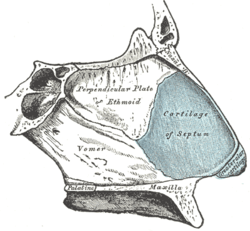

Bones and cartilages of septum of nose. Right side. | |

The fleshy external end of the nasal septum is sometimes also called columella. The nasal septum contains bone and hyaline cartilage.[2]

The nasal septum is composed of five structures:

- perpendicular plate of ethmoid bone

- vomer bone

- septal nasal cartilage

- crest of the maxillary bone

- crest of the palatine bone